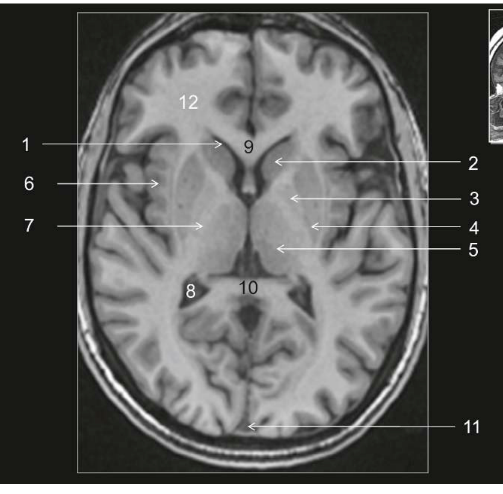

Coupe ?

Légende ?

Coupe ? Légende ?